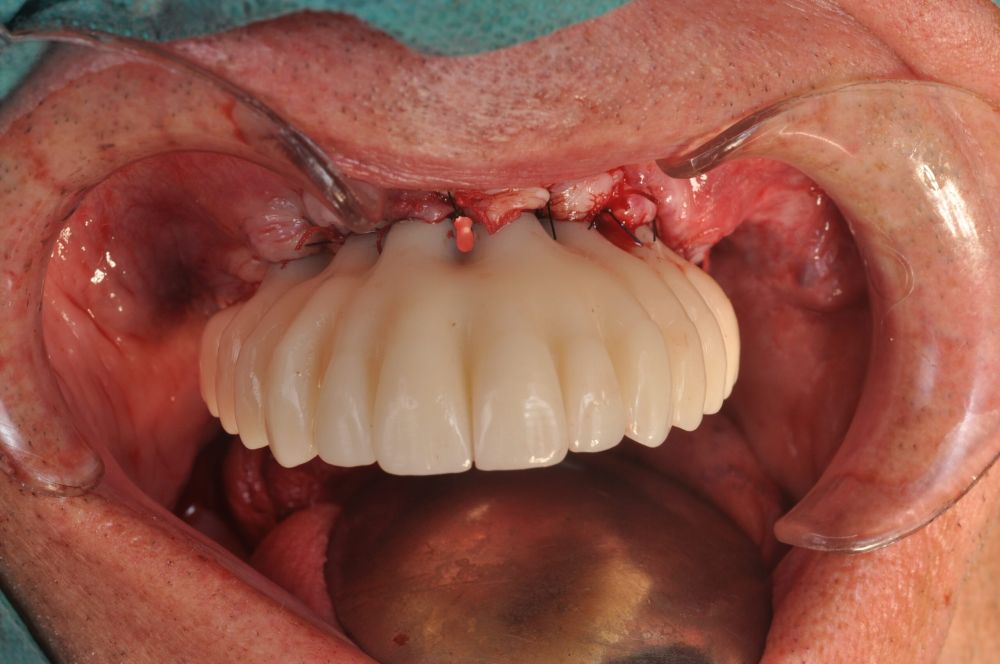

Clinical Case: A subperiosteal sintered titanium structure was fabricated with six transepithelial connections that were rehabilitated with an immediate implant supported fixed prosthesis made of PMMA. Two months later, a sintered chromium-cobalt framework with machined bases covered with acrylic resin teeth was fabricated as the final restoration. At one year follow-up, the case remains stable.